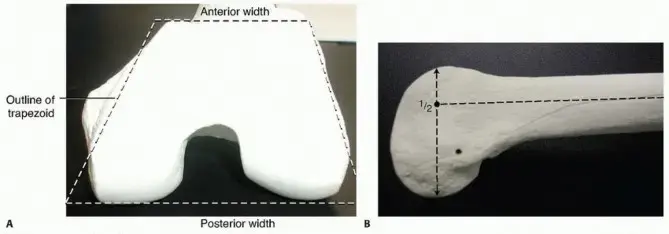

تشريح مفصل الركبة والجزء السفلي من عظم الفخذ

لفهم كسر عظم الفخذ البعيد بشكل أفضل، من المهم أن نلقي نظرة سريعة على تشريح مفصل الركبة والجزء السفلي من عظم الفخذ.

يتكون مفصل الركبة، وهو أحد أكبر وأكثر المفاصل تعقيدًا في الجسم، من ثلاثة عظام رئيسية:

أجزاء هامة في الجزء السفلي من عظم الفخذ:

*

اللقمتان الفخذيتان (Femoral Condyles):

هما بروزان مستديران في نهاية عظم الفخذ البعيدة، إحداهما داخلية (إنسية) والأخرى خارجية (وحشية). تتفصلان مع هضبة الساق لتشكيل مفصل الركبة. هذه اللقمتان مغطاة بغضروف أملس يسمح بحركة سلسة.

*

المنطقة فوق اللقمتين (Supracondylar region):

هي المنطقة الضيقة في عظم الفخذ فوق اللقمتين مباشرةً.

*

المنطقة بين اللقمتين (Intercondylar region):

هي المنطقة الواقعة بين اللقمتين الفخذيتين.